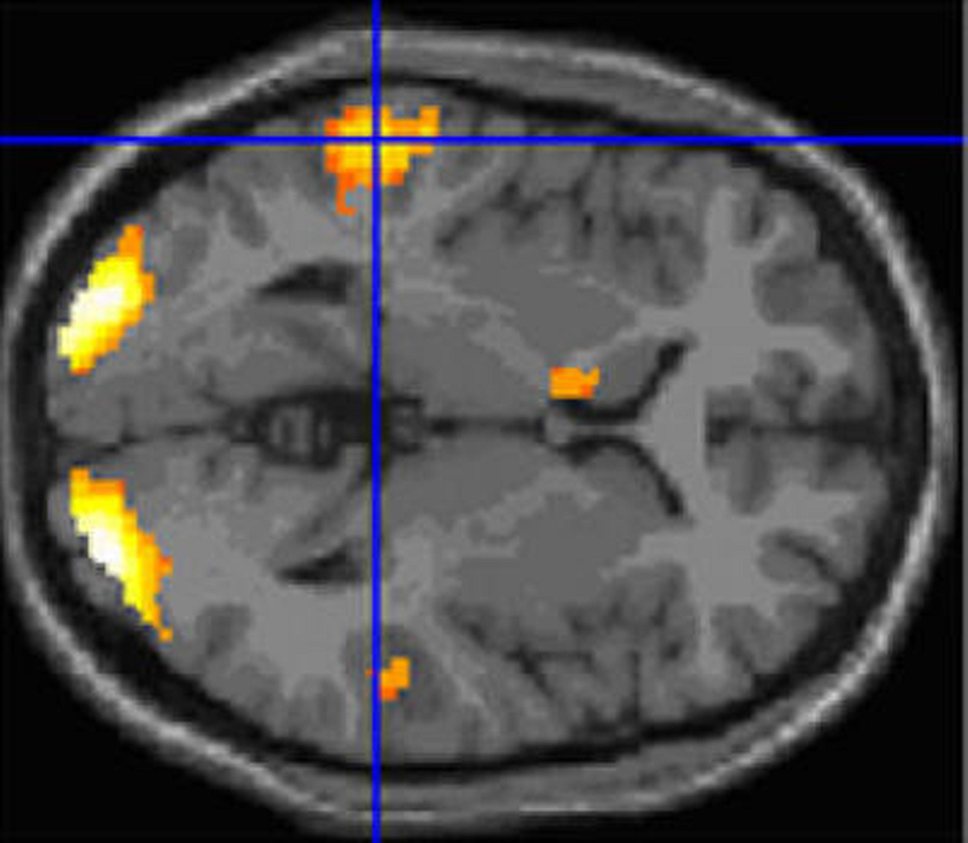

При чтении разных текстов в человеческом мозге активизируются не только несколько областей, известных как "сеть чтения",— но и зоны, ответственные за разные другие раздражители. Участники эксперимента, проведенного учеными из университета Эксетера, читали технические инструкции, отрывки из романов и любимые стихотворения во время фМРТ-сканирования. Оказалось, что чем эмоциональнее текст, тем активнее на него реагируют те области, которые отвечают обычно за восприятие музыки, а при чтении любимых стихотворений стимулируются зоны, ответственные за воспоминания. К тому же поэзия, в отличие от прозы, активно воздействует на височную долю, которая, как считается, отвечает за самоанализ. Правда, пока эксперимент проводился только среди студентов-филологов и психологов, то есть людей, занимающихся литературой и эмоциями профессионально. Исследователи не исключают, что на мозг представителей других профессий чтение действует иначе.